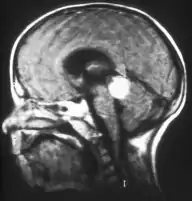

Inherited forms of retinoblastomas are more likely to be bilateral. In addition, inherited uni- or bilateral retinoblastomas may be associated with pineoblastoma and other malignant midline supratentorial primitive neuroectodermal tumors (PNETs) with a dismal outcome; retinoblastoma concurrent with a PNET is known as trilateral retinoblastoma.[15] A 2014 meta-analysis showed that 5-year survival of trilateral retinoblastoma increased from 6% before 1995 to 57% by 2014, attributed to early detection and improved chemotherapy.[16]

In about two-thirds of cases,[27] only one eye is affected (unilateral retinoblastoma); in the other third, tumors develop in both eyes (bilateral retinoblastoma). The number and size of tumors on each eye may vary. In certain cases, the pineal gland or the suprasellar or parasellar region (or in very rare cases other midline intracranial locations) is also affected (trilateral retinoblastoma). The position, size, and quantity of tumors are considered when choosing the type of treatment for the disease.

If the eye examination is abnormal, further testing may include imaging studies, such as computerized tomography (CT), magnetic resonance imaging (MRI), and ultrasound.[28] CT and MRI can help define the structure abnormalities and reveal any calcium depositions. Ultrasound can help define the height and thickness of the tumor. Bone marrow examination or lumbar puncture may also be done to determine any metastases to bones or the brain.

Aspect of trilateral retinoblastoma on MRI

Traditional ultrasound B scan can detect calcifications in the tumour while high-frequency ultrasound B scan is able to provide higher resolution than the traditional ultrasound and determine the proximity of the tumour with front portion of the eye. MRI scan can detect high-risk features such as optic nerve invasion; choroidal invasion, scleral invasion, and intracranial invasion. CT scan is generally avoided because radiation can stimulate the formation of more eye tumours in those with RB1 genetic mutation.[35]